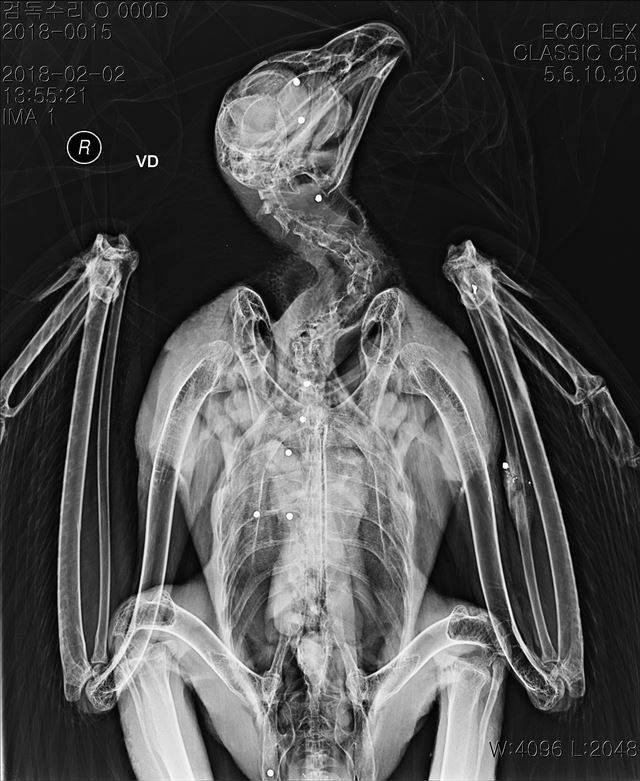

[애니칼럼] 먹잇감의 심장까지 꿰뚫는 진짜 '하늘의 제왕' 검독수리

모든 조류에게는 첫겨울 나기가 가장 어려운 과제죠. 많은 수의 검독수리도 겨울에 죽습니다. 우리나라를 찾는 소수의 어린 검독수리도 이 험난한 겨울을 버텨야 합니다. 하지만 그보다 더 큰 난관이 있습니다. 먹이 부족은 말할 나위 없거니와, 독극물에 의한 2차 중독, 셀 수 없을 정도로 깔린 고압전선, 그리고 밀렵이 있습니다. 생태계의 균형을 잡는 최상위 포식자 검독수리가 우리나라를 찾아와 어이없는 이유로 죽는 것을 막기 위해 생각해볼 점이 많을 듯합니다.(참고로 검독수리를 보호하면 그 이점이 다른 동물들에게도 적용되기에 ‘다른 종들이 비에 젖지 않도록 막아준다’는 뜻에서 검독수리와 더불어 반달가슴곰이나 황새를 ‘우산종’이라고 합니다.)

글ㆍ사진 김영준 국립생태원 동물병원 부장